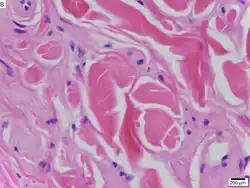

Urbach–Wiethe disease in skin biopsy with H&E stain. | |

The dermatological symptoms are caused by a buildup of a hyaline material in the dermis and the thickening of the basement membranes in the skin.[9] The nature of this material is unknown, but researchers have suggested that it may be a glycoprotein, a glycolipid, an acid mucopolysaccharide, altered collagen or elastic tissue.[6]